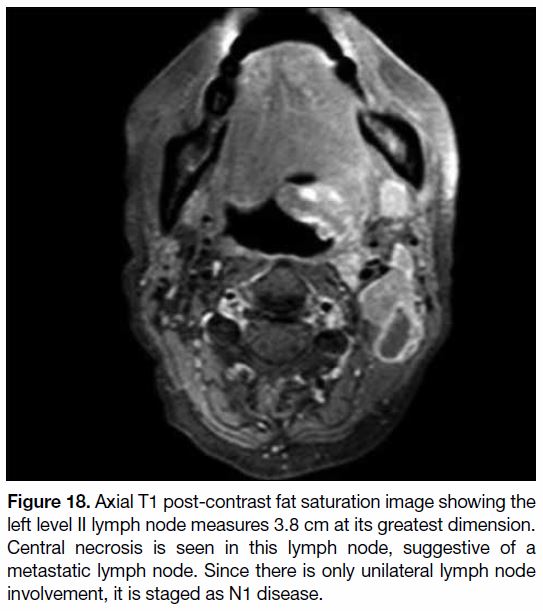

For AJCC criteria, the nodal staging is based on maximum

dimension, laterality, and site of lymph nodes. Any

lymph nodes along the midline are considered ipsilateral

nodes. Nonetheless identification of nodal metastases

relies on a short axis of lymph nodes and morphological

features including central necrosis and extranodal

extension (Figure 18).[19] In general, most cervical lymph

nodes normally should be <10 mm in their short axis. In

particular, normal retropharyngeal lymph nodes should

not exceed 5 mm in the short axis.[20] If positron emission

tomography–computed tomography is performed, any marked hypermetabolism of lymph nodes along the

expected nodal path of disease spread should raise a

suspicion of lymph node metastases, regardless of size

of lymph nodes.[21] One more point to note is that the size

of the primary tumour does not correlate with the extent

of nodal metastases.[12]

Figure 18. Axial T1 post-contrast fat saturation image showing the

left level II lymph node measures 3.8 cm at its greatest dimension.

Central necrosis is seen in this lymph node, suggestive of a

metastatic lymph node. Since there is only unilateral lymph node

involvement, it is staged as N1 disease.